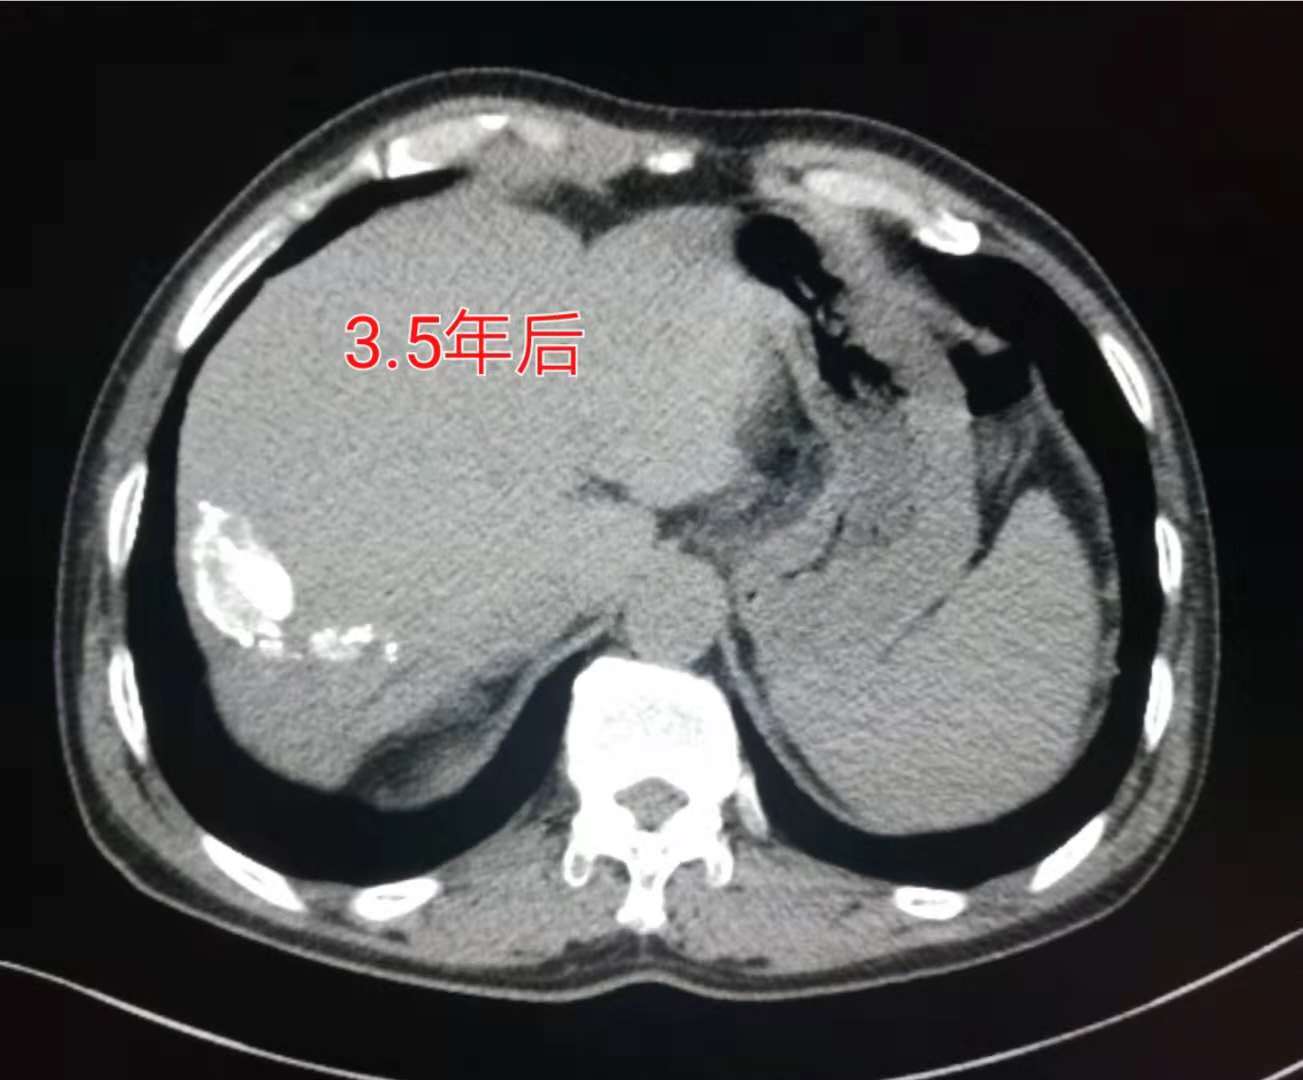

当然这个病人没有放弃治疗,选用介入栓塞配合消融治疗,三年半后还活着:

这个病人比较幸运,对治疗有效!并且三年多的时间没有发生转移和复发。